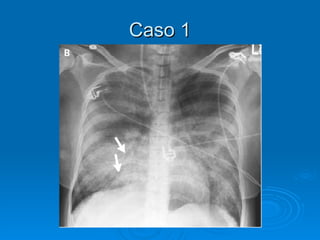

Caso 1 Pcte de 65 anos internada na terceirinha devido a um linfoma esplênico começa a cursar com dispnéia importante logo após terminar de receber 3 CGVs. Ao exame físico, apresenta estertores difusos em AHT. Como o Rx de tórax pode ajudar a diferenciar entre um edema não-cardiogênico por TRALI de um edema cardiogênico secundário a infusão excessiva de volume?

Caso 1 Pctede 65 anos internada na terceirinha devido a um linfoma esplênico começa a cursar com dispnéia importante logo após terminar de receber 3 CGVs. Ao exame físico, apresenta estertores difusos em AHT. Como o Rx de tórax pode ajudar a diferenciar entre um edema não-cardiogênico por TRALI de um edema cardiogênico secundário a infusão excessiva de volume?